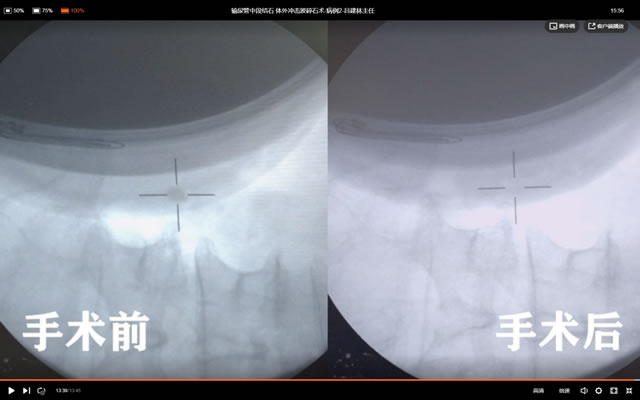

碎石效果:结石完全碎,术后即时排尿有结石排出。